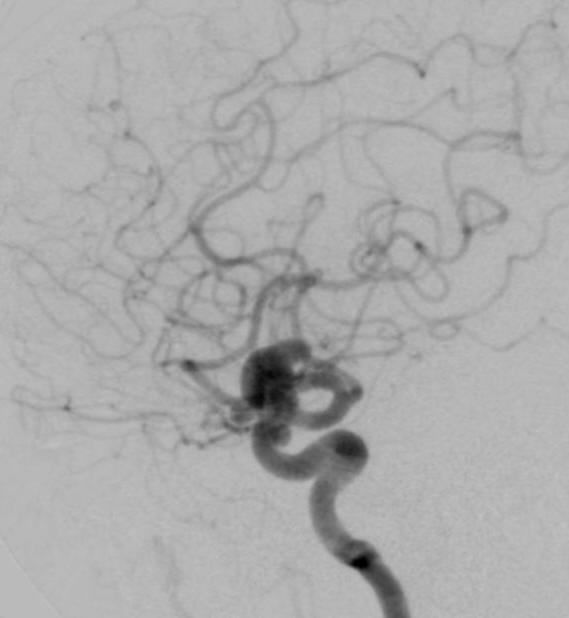

病例1